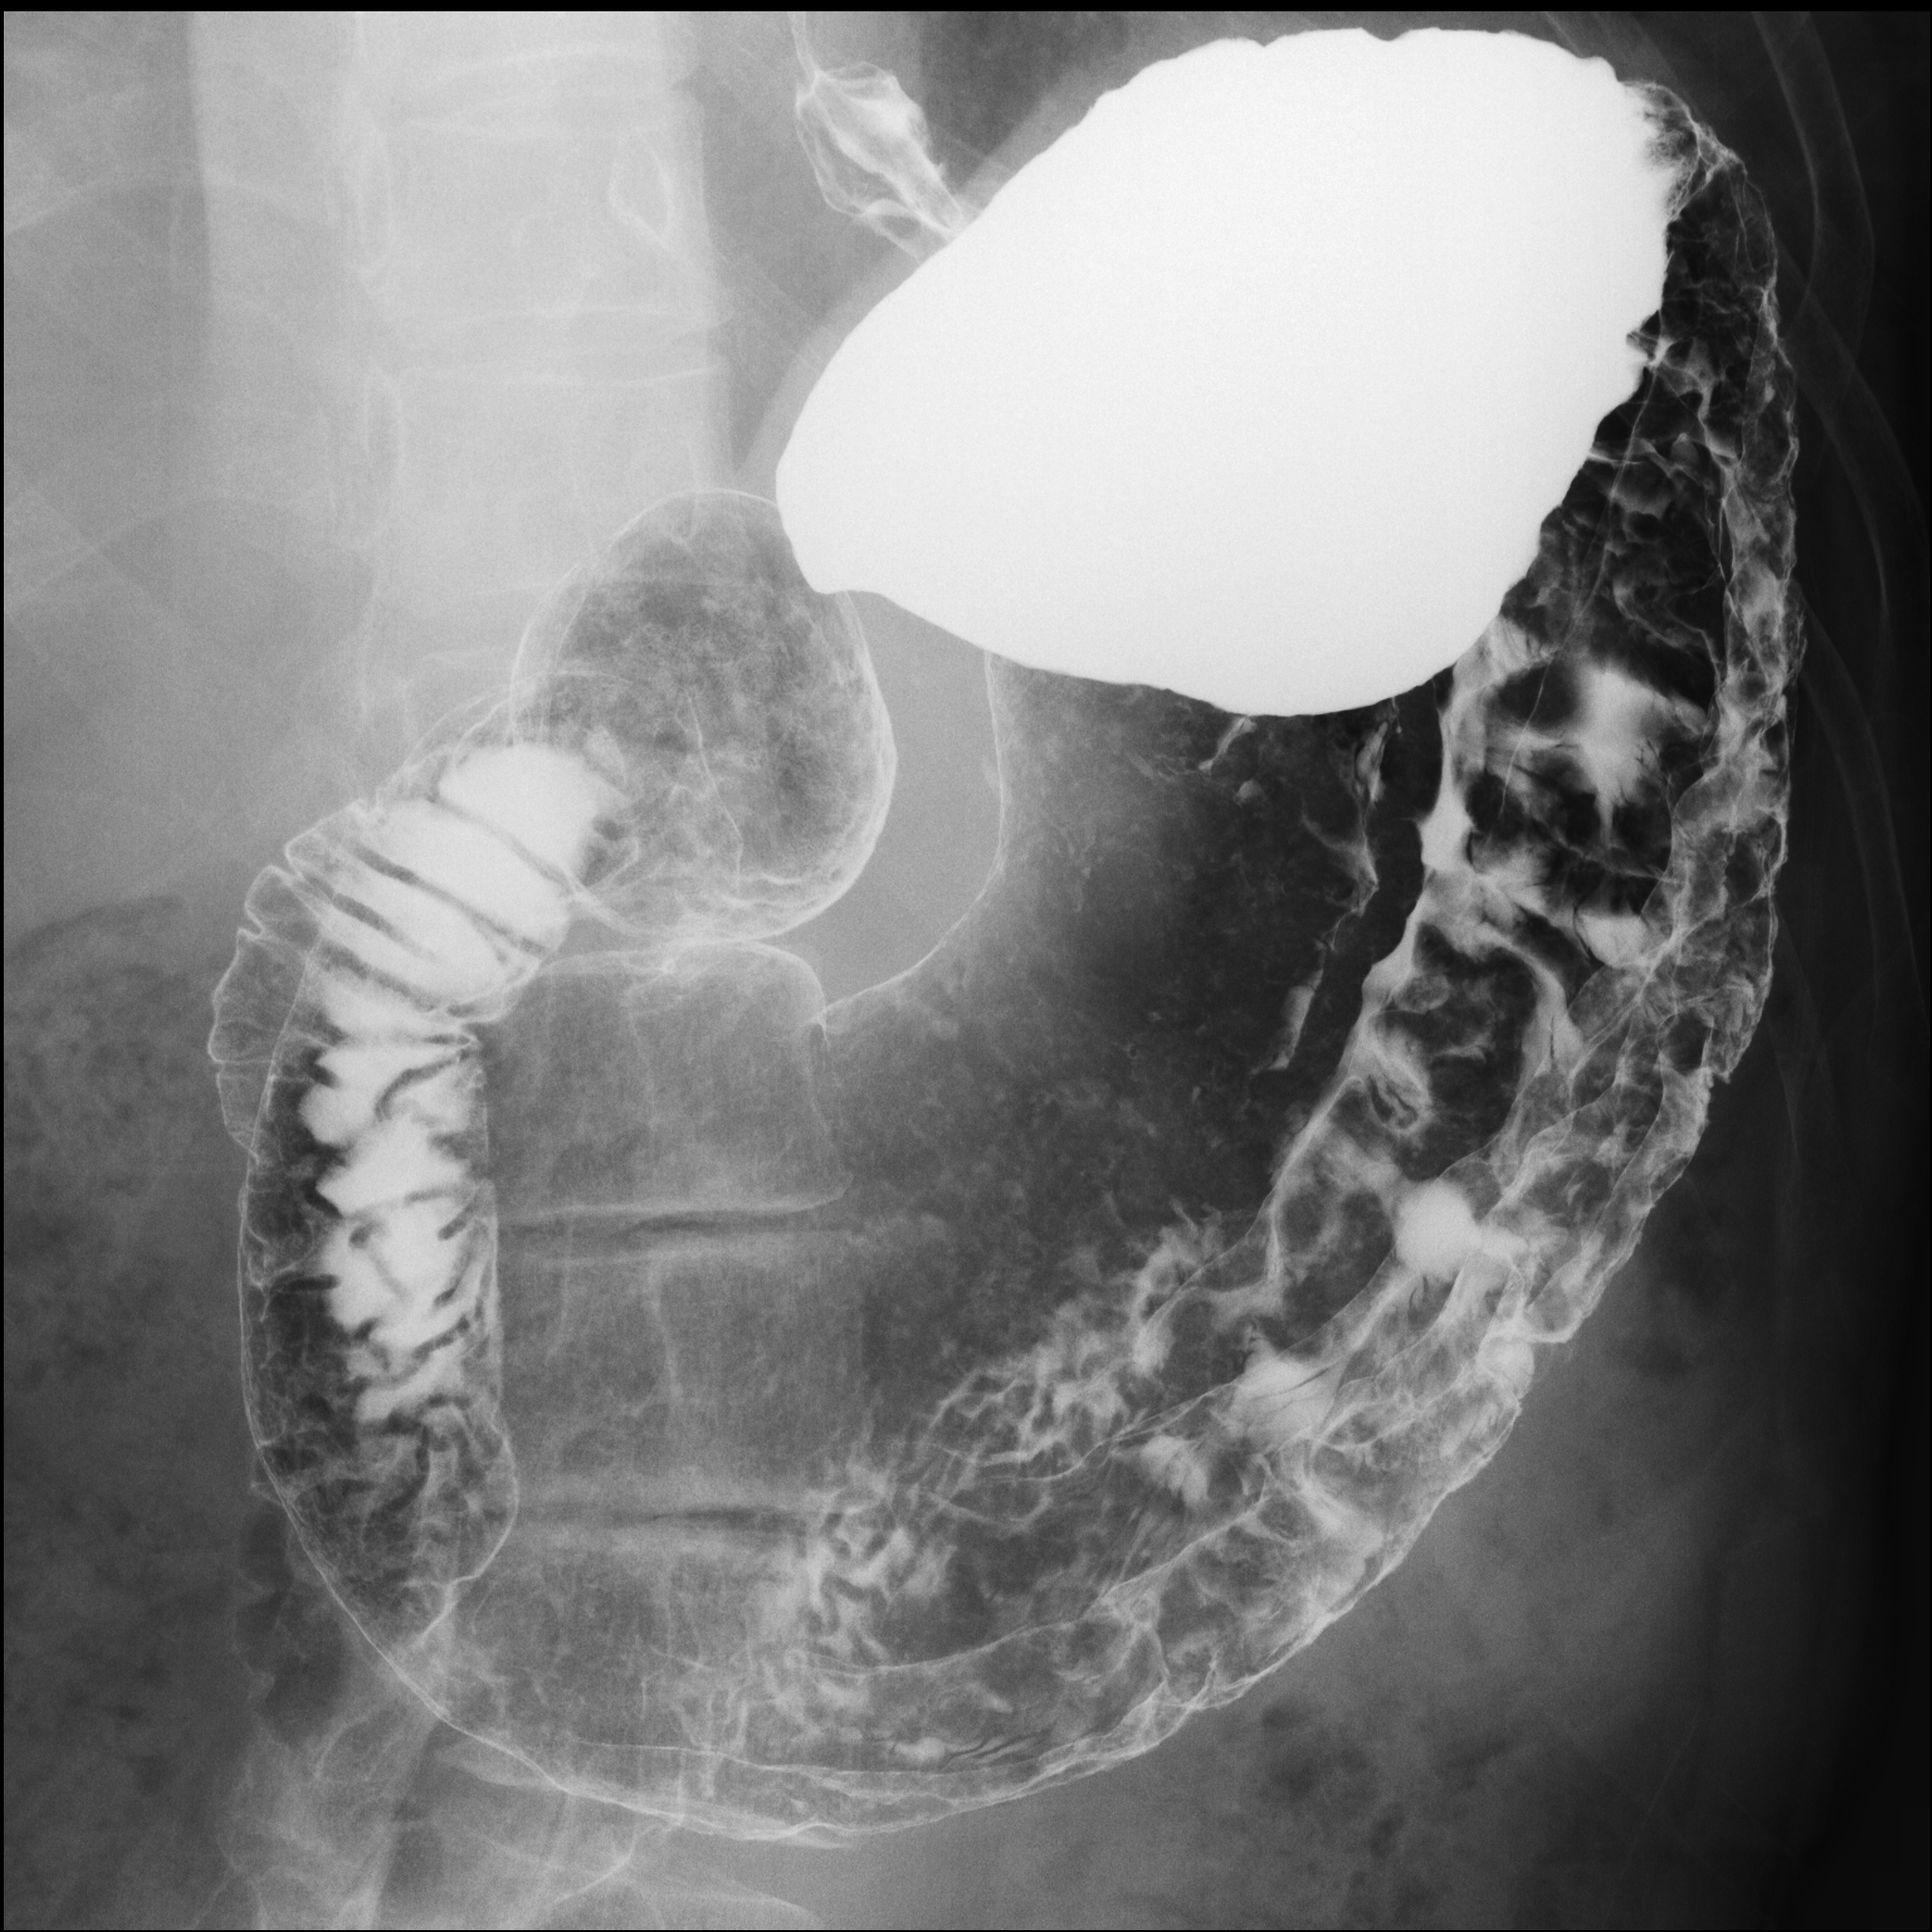

Figures 1 and 2 show the full gastric X-ray images and patch-based gastric X-ray images, respectively.

This subsection shows the experimental settings of our research. The dataset used in our study contains 815 patients' (240 gastritis and 575 non-gastritis) gastric X-ray images. Each image has a ground truth (gastritis/non-gastritis), which was determined by patient diagnosis results of endoscopic examination and X-ray inspection. All of the gastric X-ray images are gray-scale and high-resolution. The training dataset contains 200 patients' (100 gastritis and 100 non-gastritis) images. Also, the rest of the patients' (140 gastritis and 475 non-gastritis) images are included in the test dataset. In the data preprocessing stage, we divided the images into patches (299 299 pixels), , = = 35, where the sliding interval was set to 50 pixels. Besides, the patches extracted from the training dataset were labeled as , and by a radiological technologist. Note that if the regions inside of the stomach were less than 1 in a patch, it was labeled as . In addition, if the regions inside of the stomach were more than 85 in a patch, it was labeled as or . And we discarded the rest of the patches in the training dataset. As a result, we obtained , and whose number of patches were 48,385, 42,785 and 45,127, respectively.